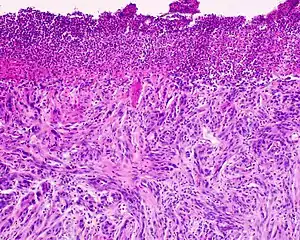

Desmoplastic melanoma

Desmoplastic melanoma is a rare cutaneous condition characterized by a deeply infiltrating type of melanoma[2]: 696 with an abundance of fibrous matrix.[3] It usually occurs in the head and neck region of older people with sun-damaged skin.[3] Diagnosis can be difficult as it has a similar appearance to sclerosing melanocytic nevi as well as some nonmelanocytic skin lesions such as scars, fibromas, or cysts.[3]